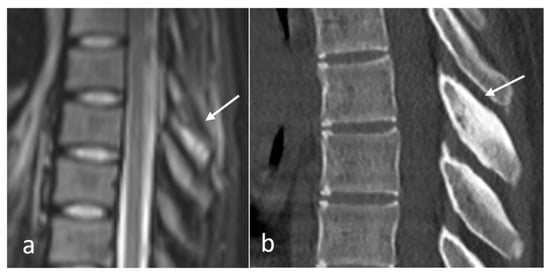

These fractures can be readily visualised on a plain film or CT, where a displaced fragment without a sclerotic edge can be seen. MR demonstrates bone marrow oedema (T2 hyperintensity) at the fracture site with frequent oedema within the interspinous ligament. Chronic non-union is a complication and is characterised by sclerosis and/or irregularity of the fracture line (Figure 8) and by resolution of oedema on MRI.

Figure 8.

Sagittal CT image demonstrating a non-united fracture of C2 spinous process (white arrow).